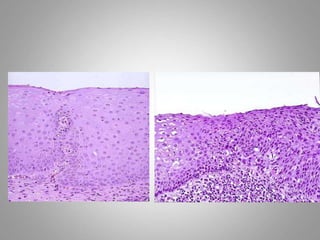

Dysplasia :

– Definiton: a loss in the uniformity of the individual

cells and a loss in their architectural orientation.

– Occurs mainly in the epithelia

– Dysplastic cells shows a degree of : pleomorphism,

hyperchromasia,increased mitosis and loss of

polarity.

• Dysplasia does not mean cancer

• Dyplasia does not necessarily progress to

cancer

• Dysplasia may be reversible

• If dysplastic changes involve the entire

thickness of the epithelium it is called :

CARCINOMA IN-SITU

• Carcinoma in-situ

– Definition: an intraepithelial malignancy in which

malignant cells involve the entire thickness of the

epithelium without penetration of the basement

membrane.

– Applicable only to epithelial neoplasms.

Dysplasia : – Definiton:a loss in the uniformity of the individual cells and a loss in their architectural orientation. – Occurs mainly in the epithelia – Dysplastic cells shows a degree of : pleomorphism, hyperchromasia,increased mitosis and loss of polarity.

• 60.

• Dysplasia doesnot mean cancer • Dyplasia does not necessarily progress to cancer • Dysplasia may be reversible • If dysplastic changes involve the entire thickness of the epithelium it is called : CARCINOMA IN-SITU

• 62.

• Carcinoma in-situ –Definition: an intraepithelial malignancy in which malignant cells involve the entire thickness of the epithelium without penetration of the basement membrane. – Applicable only to epithelial neoplasms.